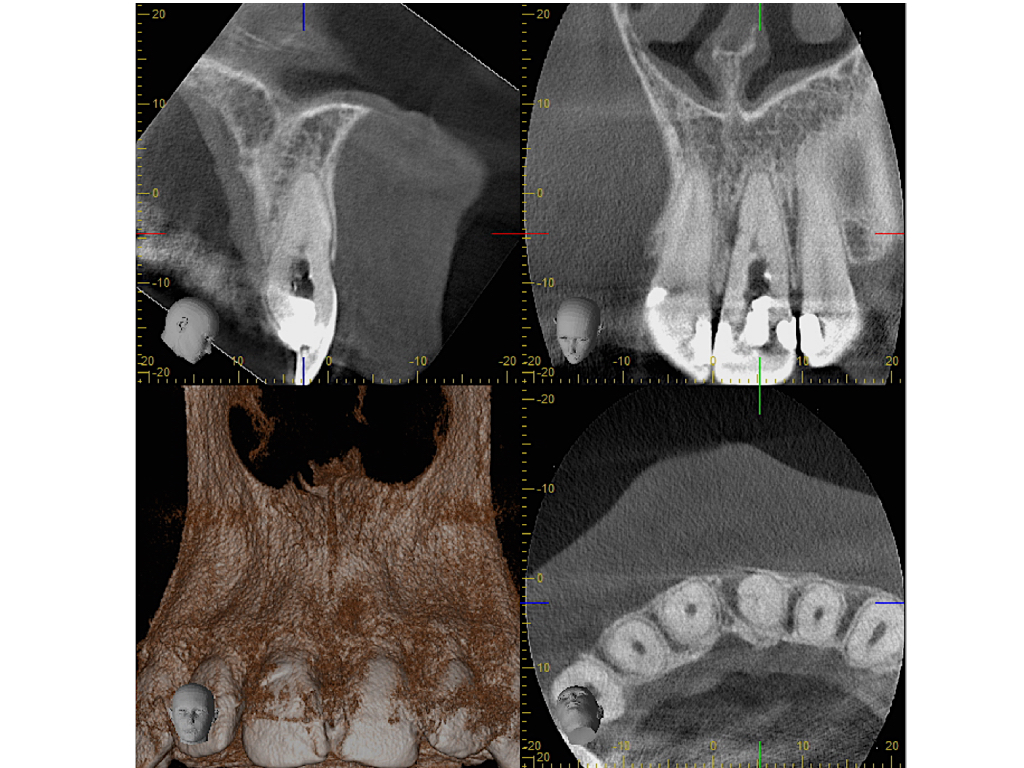

WS_Fallvorstellung15_12_1.003

Lateraler Kanal (2)